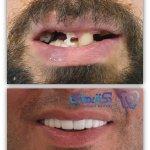

همچنین ایشان در دی ماه سال 2013 میلادی سرتیفیکیت دوره پیشرفته ایمپلنت های دندانی را دریافت کردند. علاوه ازاین، اخیرا در پی تلاش برای بروز رسانی اطلاعات علمی و همگامی با دانش روز دنیا سرتیفیکیت دوره پیشرفته جراحی و درمان ریشه دندان (عصب کشی) را در سال 2016 میلادی از دانشگاه جنوا ایتالیا دریافت کرده اند.

گالری